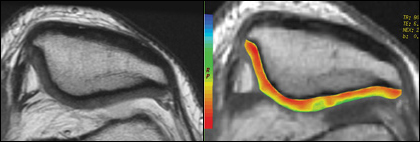

cartigram patellofemoral

cartigram lateral mri cartigram

Patellofemoral cartilage